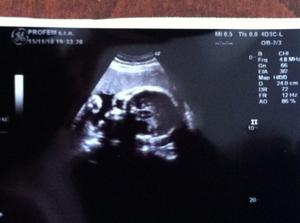

Ultrazvuky a bruska

krasne 4D fotky 🙂